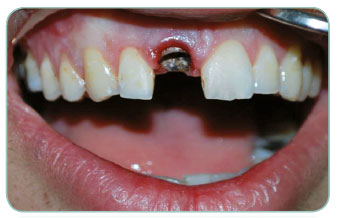

On the back of a trauma our patient had lost his up front teeth. We have applied one Implant together with a zirconium porcelain.